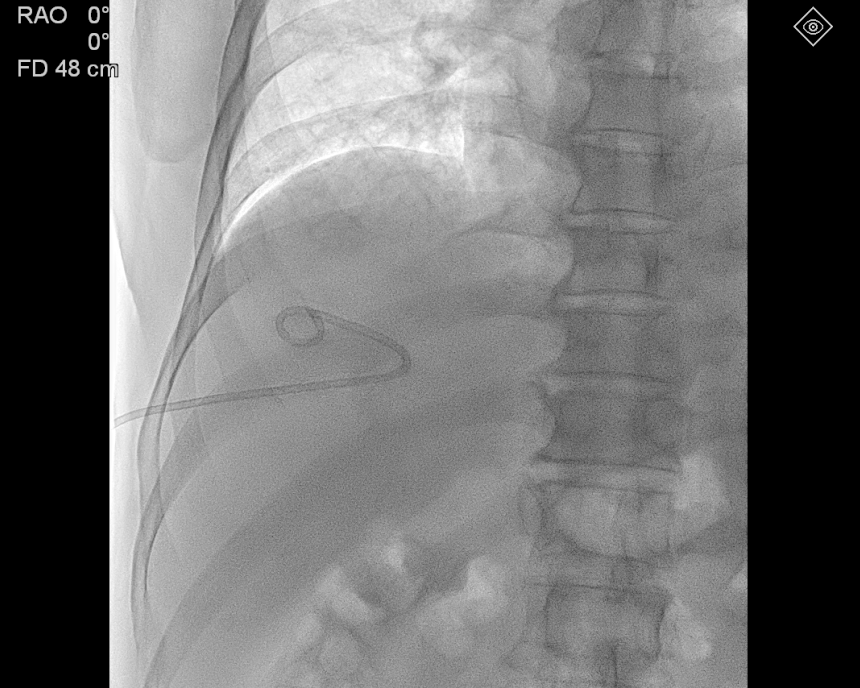

경피적 삽관술(PCD)을 시행하였고, 배농 된 균주를 배양검사 접수를 하고 환자분은 입원하게 되었다.

며칠 뒤 입원 중인 환자분의 상태를 확인해 보았고,

환자분은 다행히 염증수치의 호전을 보이며, 잘 회복하고 있는 상태였다.